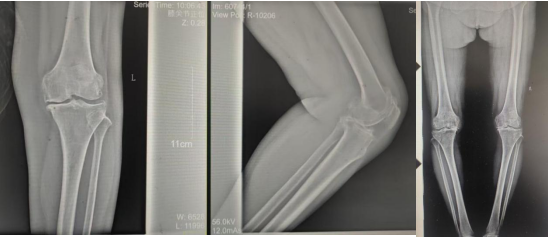

术前影像资料

张女士于10年前劳累后左膝疼痛,,,,,干活后疼痛较重,,,,,阴雨天及受凉时疼痛显着,,,,,行走时可闻及枢纽内异响,,,,,时有“打软腿”征象,,,,,曾到周围多家医院诊治,,,,,给予膝枢纽针灸、膏药外贴、口服药物等“守旧”治疗,,,,,治疗后疼痛症状略有好转,,,,,但易复发;;近2年患者左膝枢纽疼痛逐渐加重,,,,,行走跛行,,,,,下蹲及上下楼梯难题,,,,,活动时疼痛显着,,,,,休息、守旧治疗后疼痛无显着好转。。。。。。

张女士的邻人看她上下楼云云难题,,,,,日常生涯都很受影响,,,,,因其以前在我院看过腰椎,,,,,效果优异,,,,,故先容张女士来我院找万昌胜主治医师举行咨询问诊。。。。。。万医生相识情形后带她到我院枢纽外科举行更专业的诊治。。。。。。枢纽外科门诊医师连系症状体征及影像学检查,,,,,建议入院手术治疗,,,,,以“左膝骨性枢纽炎伴膝内翻、高血压病”收住入院。。。。。。